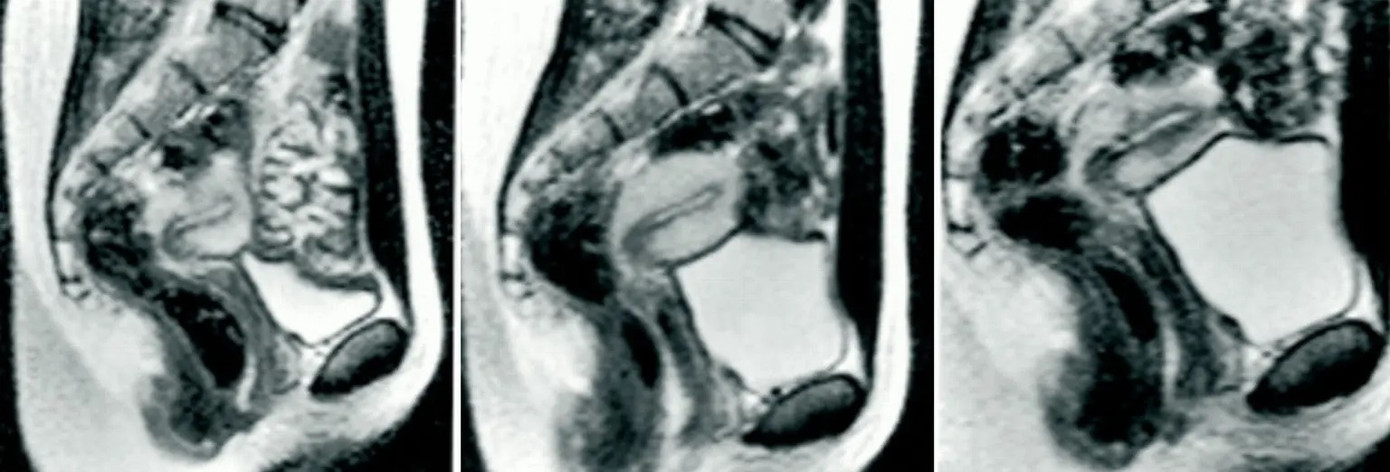

Ida và Jupp đã được kiểm tra thể chất bên trong máy chụp cộng hưởng từ sau khi bạn của họ, nhà khoa học người Hà Lan Menko Victor “Pek” van Andel, bắt đầu khám phá những gì xảy ra bên trong cơ thể chúng ta khi làm “chuyện ấy”.

Những hình ảnh này đã trở thành tâm điểm của một mục cực kỳ nổi tiếng trên Tạp chí Y học Anh (BMJ) vào năm 1999. Giờ đây, sự quan tâm đã được khơi dậy trở lại do câu chuyện và những hình ảnh đang lan truyền trên TikTok dựa trên một bài báo năm 2019 từ Vice .

Thế nhưng, kết quả chụp cộng hưởng từ cho thấy “cậu nhỏ” có hình dạng của một chiếc boomerang, nghĩa là nó uốn cong vào bên trong theo hình dạng của cơ thể phụ nữ mà không gây đau đớn cho người đàn ông khi cương cứng.

Phát hiện này rất lớn, dẫn đến một nghiên cứu chính thức được thực hiện từ năm 1991 đến 1999 bởi Ida và Pek, kết quả của chúng đã được công bố trên tạp chí y học nổi tiếng của Anh BMJ.